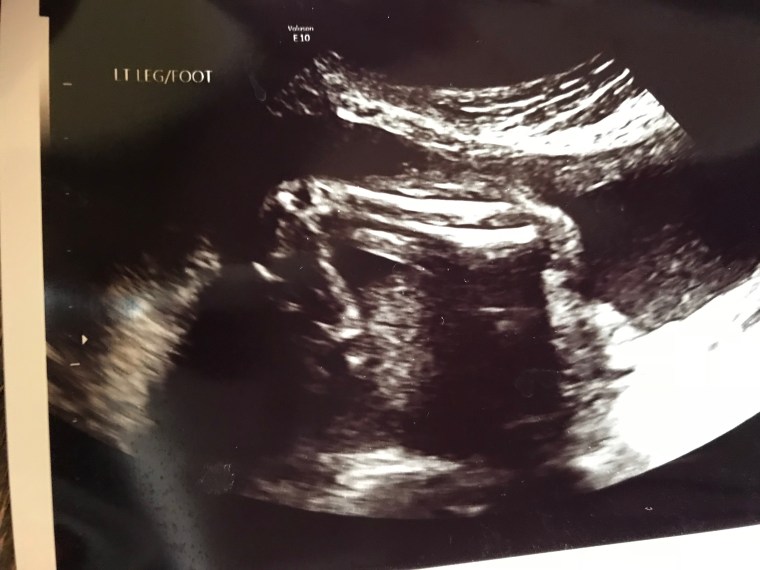

It was the very end of our 16 week ultrasound when the technician said “well baby is looking great! There’s just one little thing here, her left foot is turned in, so the doctor will chat with you about that. Everything else is absolutely perfect!” it was a cheerful voice but you could tell it was awkward for her to say, how do you deliver news like this to a parent? She guided the ultrasound probe around to zoom in on her foot and showed us how compared to the other foot you could see all the foot bones in one plane which indicated that it was turned in. She didn’t use the term clubfoot until I said it. It was obvious she was politely trying to tip toe around things until the doctor came in so that he could do the talking. I asked a handful of questions which she tried to answer vaguely and kept reiterating that the doctor would have a lot more info for us.

The technician left the room and my husband and I looked at each other with concern but didn’t really say anything. It was quite a wait before the doctor came in, he zoomed in on the screen and made few comments confirming what she had told us, that baby’s foot was clubbed, at which point I drilled him with questions about how everything else was looking? Did she look healthy? How was her heart? How did her nuchal translucency length look? Any other obvious genetic deformities? My husband sat there wide eyed, he knew exactly what was going on, this is what I do when there’s a serious medical situation, I don’t let on how serious things are until I have an answer and an explanation and then I let him in on the details. He looked at me and back to the doc then to me and then to the doc trying to grasp what we were saying. I could tell he knew I was scared which in turn made him very concerned.